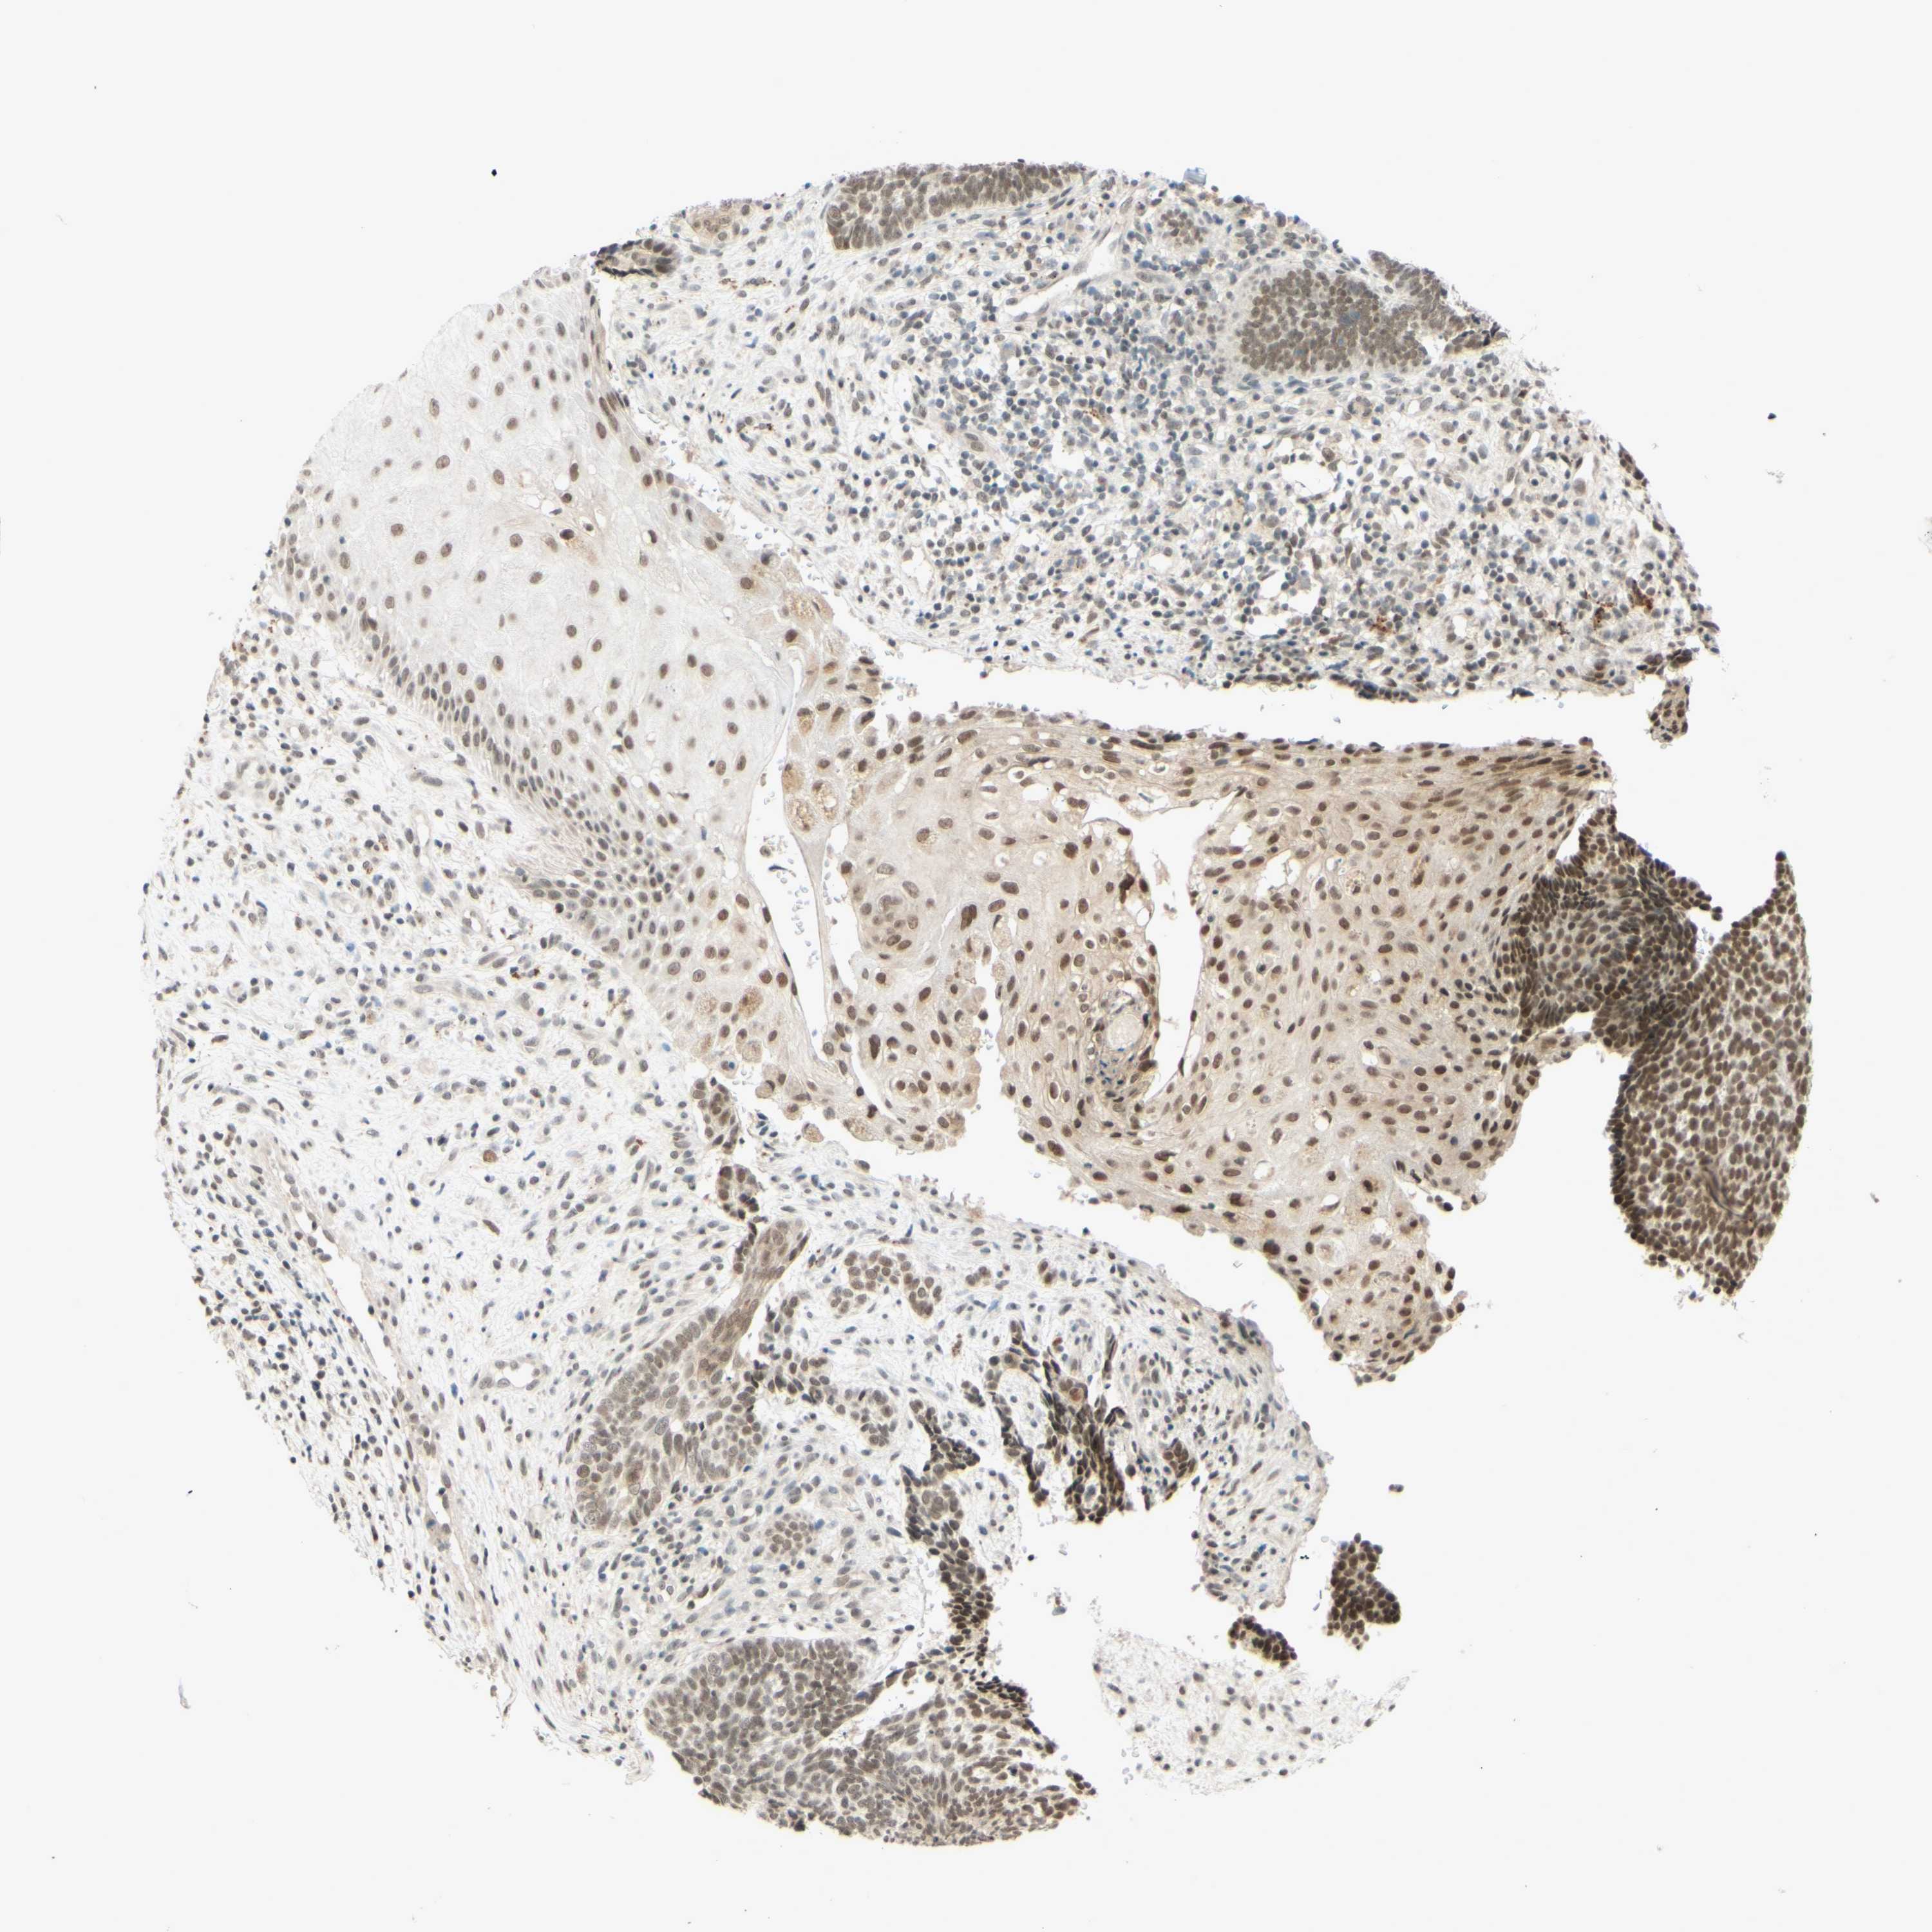

SKIN CANCER - Protein expressioni

A mouse-over function shows sample information and annotation data. Click on an image to view it in a full screen mode. Samples can be filtered based on level of antibody staining by selecting one or several of the following categories: high, medium, low and not detected. The assay and annotation is described here.

Each image is clickable and will lead to virtual microscopy that enables deeper exploration of all samples and also displays staining intensity scores, fraction scores and subcellular localization as well as patient and tissue information for each sample.

Antibody HPA019127

Squamous cell carcinoma, NOS